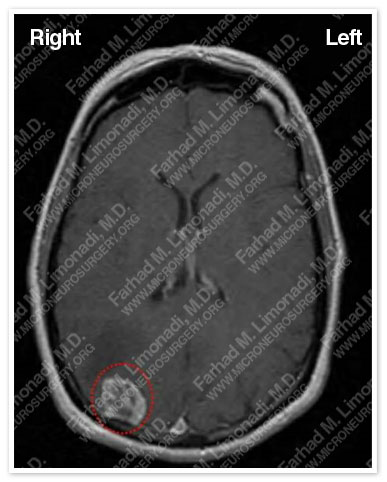

Imaging

An MRI of her brain disclosed a right occipital tumor (outlined in a red dotted circle).